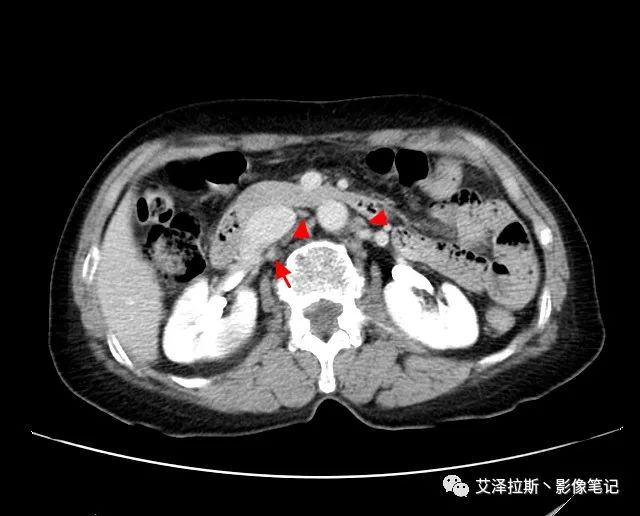

【基本情況】 患者,女性,66歲,貧血。

圖1 平掃+增強各期

【影像所見】 胃竇部狹窄,胃壁環形增厚,小彎側見一巨大潰瘍,周圍伴“環堤征”,漿膜面不完整,胃周脂肪見網格狀條索影,病灶與肝臟左葉、胰腺鉤突脂肪間隙消失,增強掃描病灶明顯強化。引流區內約15個區域淋巴結受累。

【診斷意見】 胃竇部胃癌(T4N3期) 該病例腫塊突破漿膜層,與肝臟左葉、胰腺鉤突分界不清,脂肪界面消失,定為T4期; 受累及的淋巴結為15個區域,定為N3; 有無遠處轉移尚不明確,所以M期暫時無法確定。